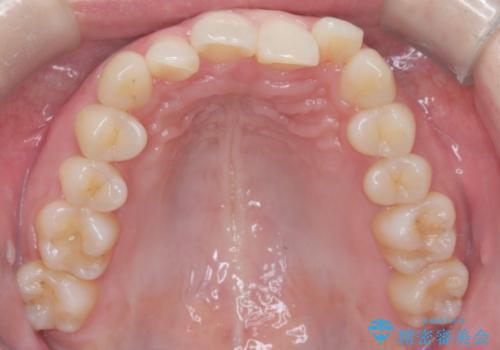

インビザライン矯正|下顎前歯1本抜歯でスムーズに歯列改善(1年で完了)

- 患者様は、下顎前歯のガタつきを改善したいとのことで来院されました。診察の結果、スペース不足により前歯が重なっている状態でした。抜歯をせずに並べると前歯が前方に突出してしまうため、下顎の前歯を1本抜歯し、インビザラインで矯正する治療計画を立てました。できる限り追加のアライナーを使用せずに治療を完了できるよう、初回の治療計画を慎重に設計しました。

下顎前歯を1本抜歯し、歯列のスペースを確保。その後、インビザラインを用いて計画通りに歯を移動させ、噛み合わせも整えました。患者様の協力もあり、ゴムかけなどを適切に行い、予定通り1年で治療を完了。追加アライナーを使用することなく、計画通りに治療を終えることができました。患者様からは「思ったより早く終わり、仕上がりにも満足している」と喜びの声をいただきました。